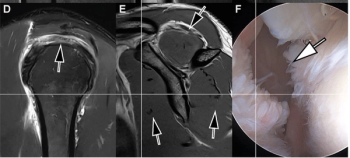

Researchers found that the use of seven-minute threefold parallel imaging-accelerated deep learning 3T MRI had 89 percent sensitivity for supraspinatus-infraspinatus tendon tears and 93 percent sensitivity for superior labral tears.